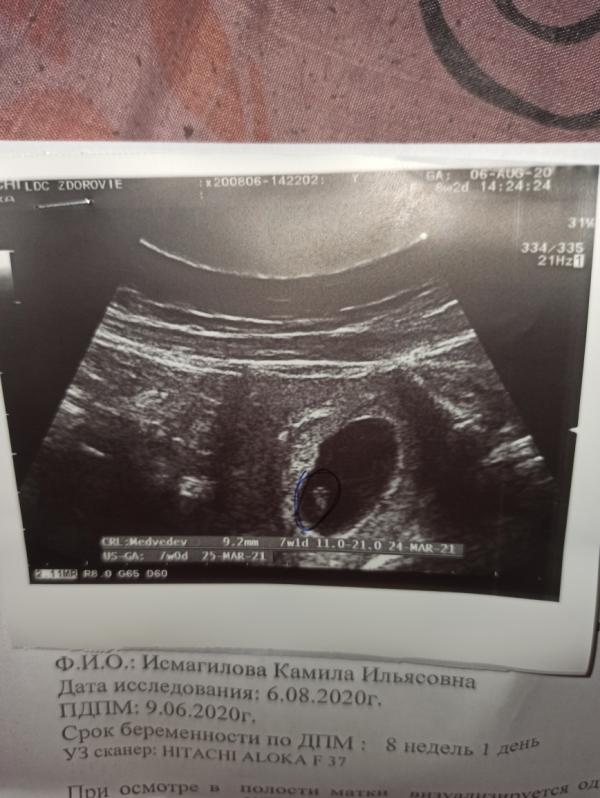

Камила·Мама двоих (1 год, 4 года)

Была на УЗИ)) сердечко бьётся)))